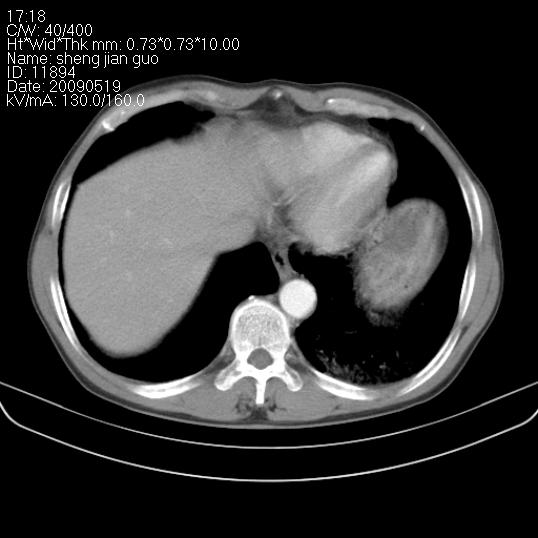

以下是引用zjzjr在2009-5-19 17:25:00的发言:[br]支持楼主考虑,另左肺下叶阻塞性炎症。

以下是引用zhao_bin2008在2009-5-19 17:48:00的发言:[br]支持左肺下叶周围型肺癌并阻塞性肺炎。

以下是引用杀毒软件在2009-5-19 17:36:00的发言:[br]支持楼主

以下是引用zsl6918在2009-5-20 7:10:00的发言:[br]左侧中心型肺癌!